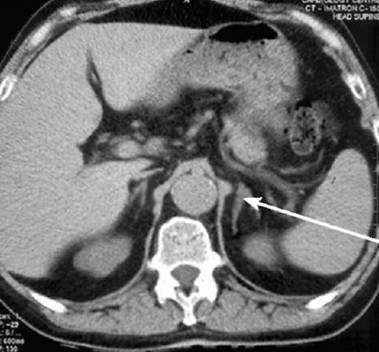

Аденома надпочечника – фото МРТ-снимка пациента с доброкачественной опухолью правого надпочечника: